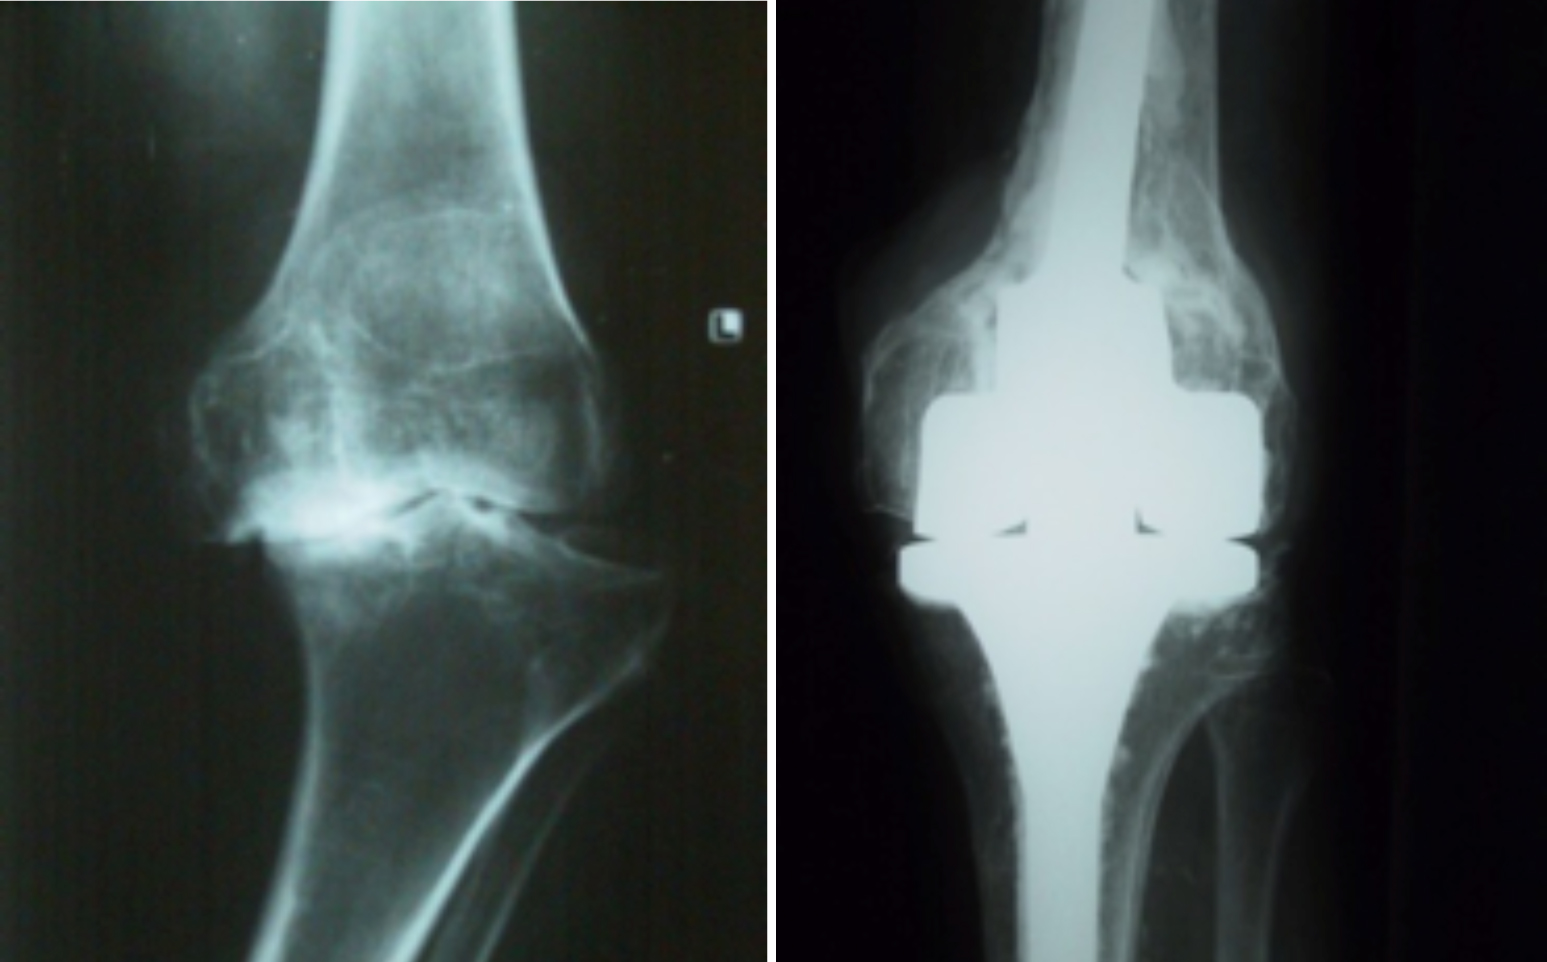

一、人工关节置换 各种晚期骨关节病的关节置换手术治疗是北京清华长庚医院关节外科中心的一大特色,包括股骨头坏死、髋膝骨关节炎、类风湿关节炎、强直性脊柱炎、髋关节发育不良、关节强直、超过80岁的超高龄股骨颈骨折患者的关节置换手术等,我中心在人工关节初次置换及翻修上作了大量工作,置换的难度和手术效果方面已达到国际先进水平,导航下全膝关节置换术:大大提高膝关节置换手术的精确度。

局限性关节置换手术(UKA)

全膝关节表面置换手术(TKA)

铰链式人工膝关节置换手术(HK)膝关节周围韧带严重破坏

国内首例膝关节置换术后Felix IIB型胫骨假体周围骨折翻修术